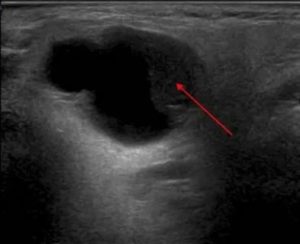

Как выглядит киста яичника на УЗИ

Основной признак кисты яичника на УЗИ – формирование на его теле полого отростка. Он отличается от нормального фолликула тем, что, на протяжении цикла, никак не меняется. К тому же, такое новообразование имеет больший размер.

На снимке УЗИ, киста яичника выглядит черным пятном, размером от 3 до 20 см.

Фолликулярная

Выглядит на УЗИ однокамерным гипоэхогенным образованием округлой формы. Его стенки – очень тонкие, а контур – ровный и четкий.